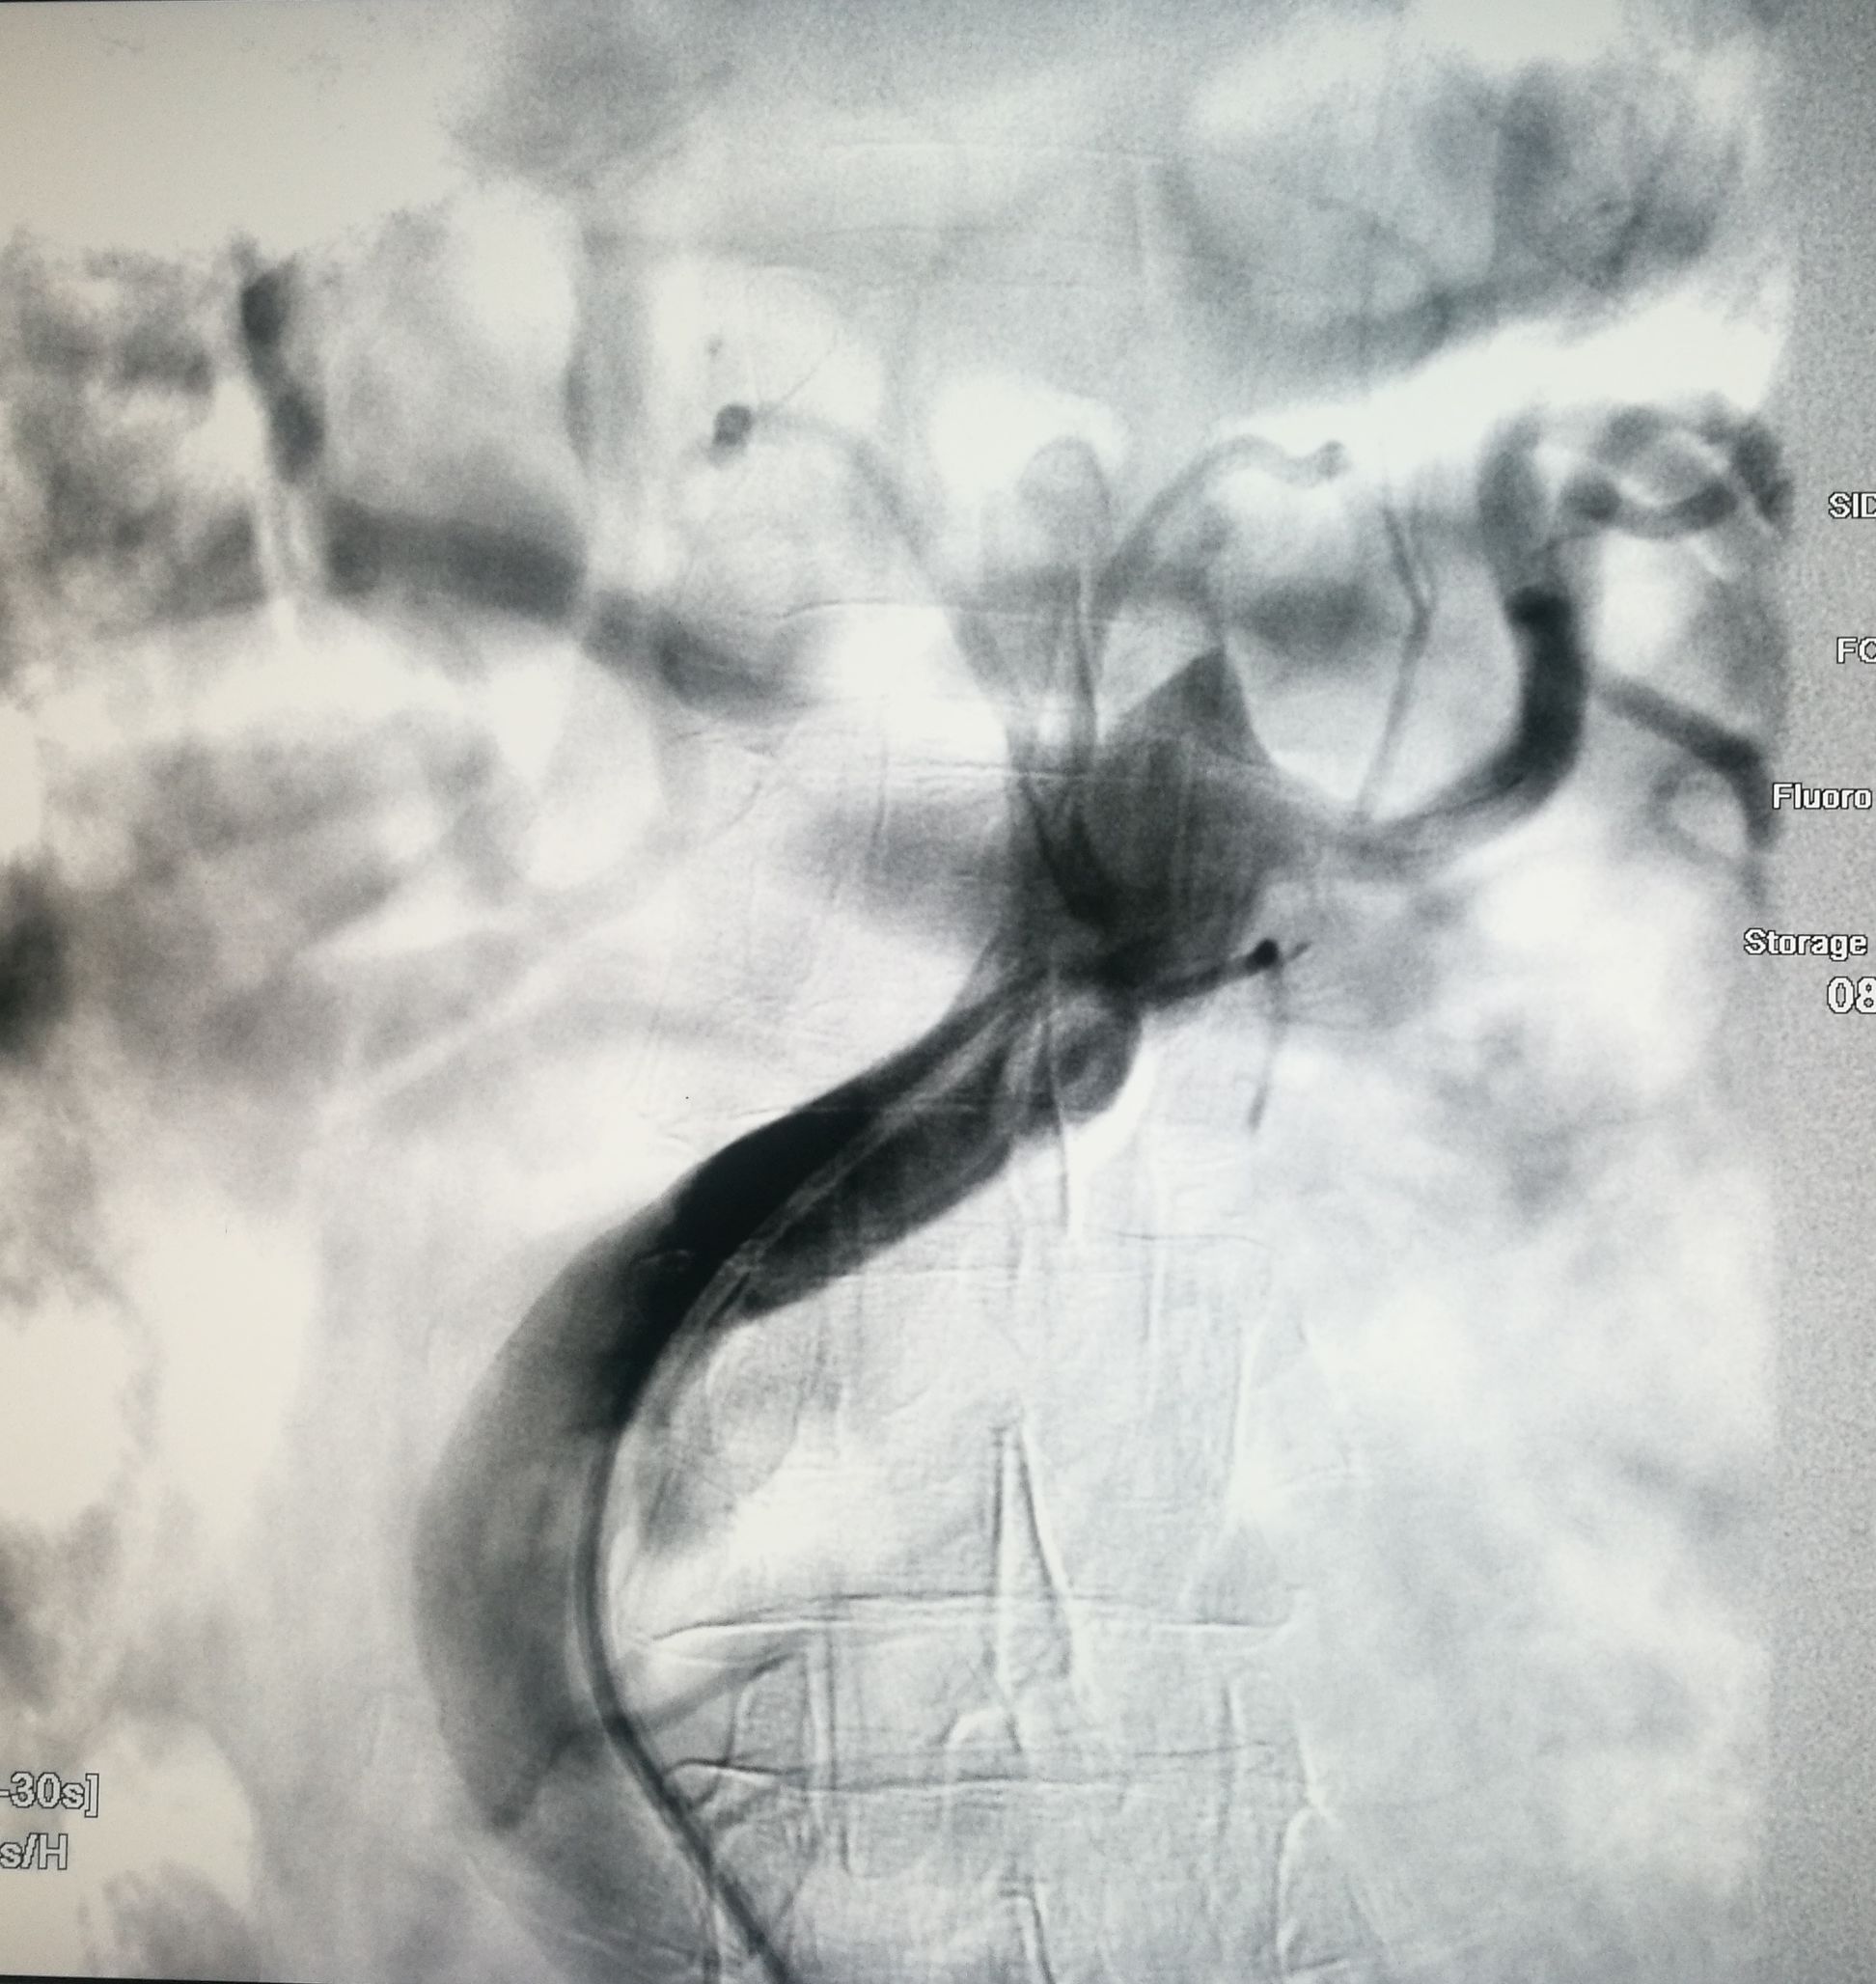

手术在局麻下进行,经右股动脉穿刺置管到升主,经左桡动脉穿刺植入金标猪尾导管,造影,为确认真假腔,加做右前斜位造影,确认股动脉导管在真腔内,测量后植入覆膜支架。由于扭曲严重(腹主,膈肌附近,弓降),支架最初并未贴服大湾侧,支架送过锁骨下动脉后适当回撤,请拉释放导丝,此时支架整体向大弯侧轻微移动,考虑应力已经得到缓解。完全释放支架,定位良好,封堵完全无内漏。